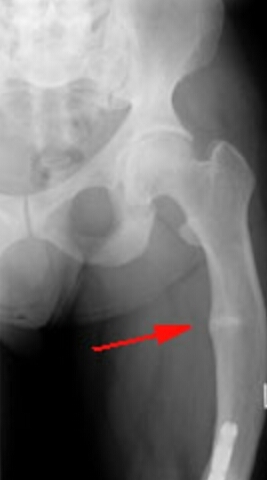

What is the diagnosis? What radiographic features make that so (features both on the xray and off)?

Ostomalacia

osteopenia, coarsened trabeculation, LOOSER LINES, bowing of the femur

basilar invagination, acetabular protrusion